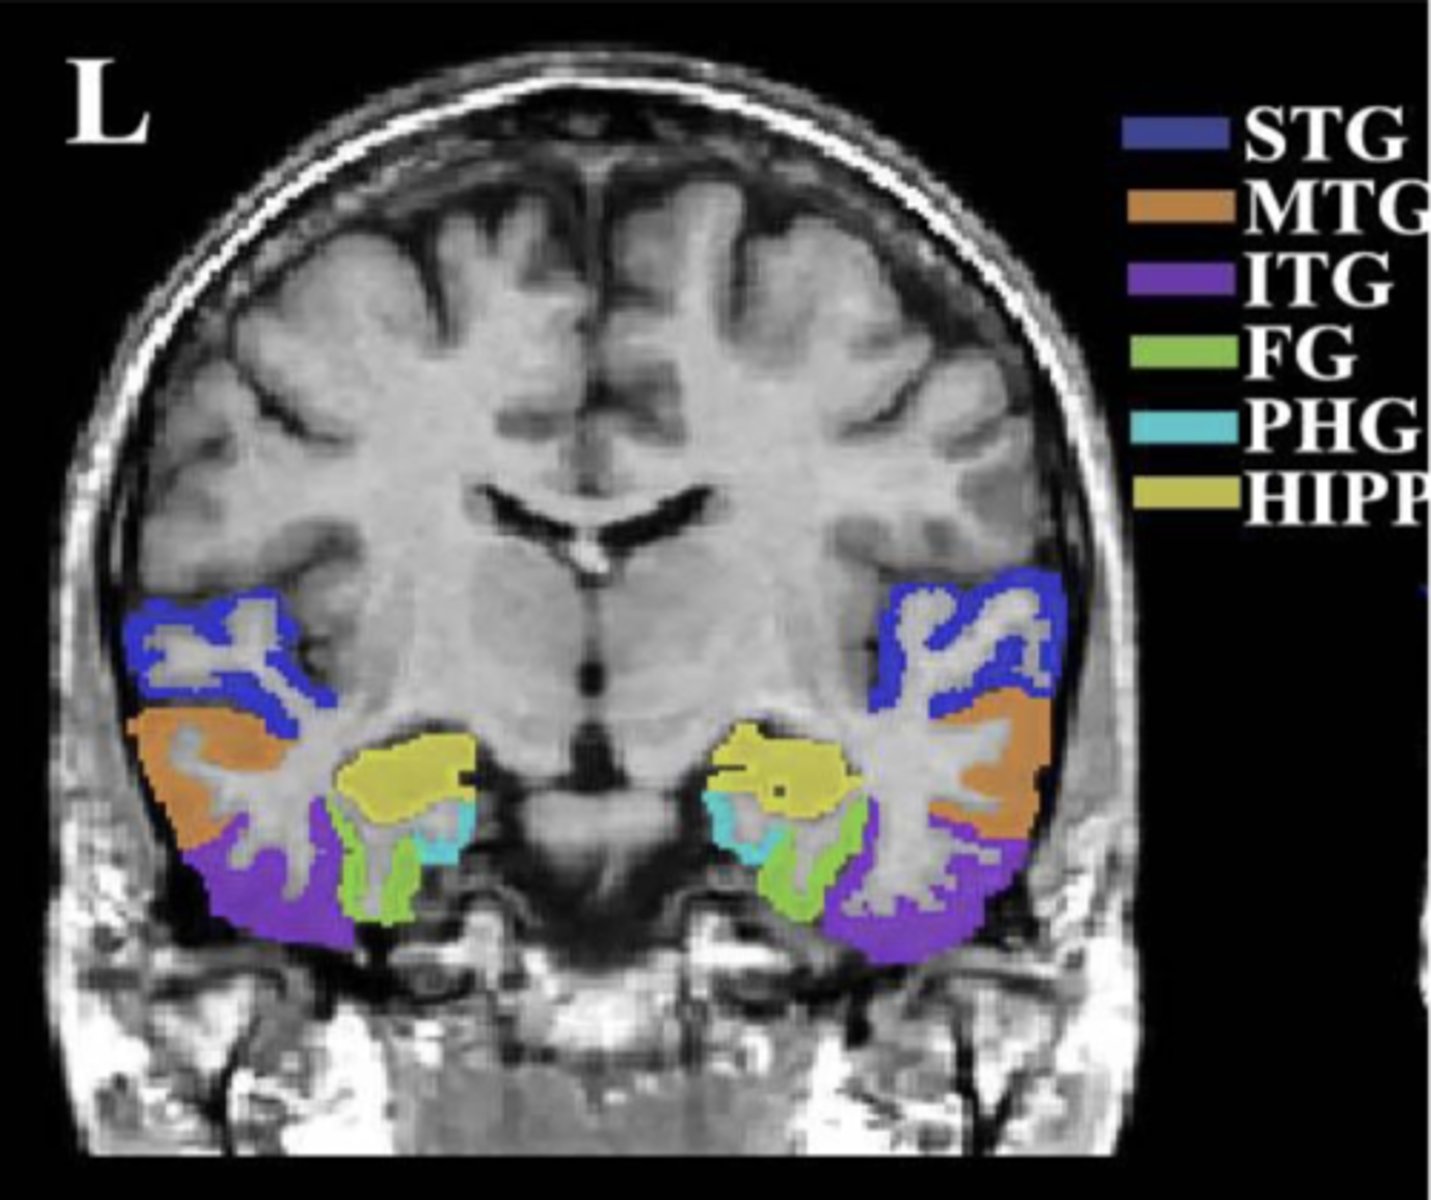

temporal lobe (coronal view)

insula

circled in red, next to STG

superior temporal gyrus (STG)

dark blue area

middle temporal gyrus (MTG)

orange area

inferior temporal gyrus (ITG)

purple area

fusiform gyrus (FG)

green area

parahippocampal gyrus (PHG)

light blue area

hippocampus (HIPP)

yellow area